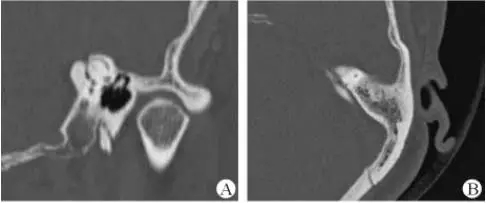

1、上半規管裂綜合征

內耳結構非常微妙。即使是內耳中大頭針樣的孔洞也能造成平衡失調。患者常常不敢進行如走路或轉頭的日常活動。此罕見疾病,醫學專家預估至少影響著人口的1%。可造成惡心,眩暈以及對噪聲極高的敏感性。病人還常常抱怨他們能聽到血管跳動的聲音。其中一位患者曾告訴耳科專家,他都能聽到自己轉動眼睛的聲音。

診斷及治療

醫生若懷疑此病將會安排內耳CT掃描。在大多數案例中,一旦此病被耳鼻喉科醫生或其它聽力健康專家確診,則可實行手術治療。外科手術風險包含聽力損失以及神經損傷;重建及復原需內耳的治療以及大腦的重塑。

2、膽脂瘤

另一個不常見的疾病叫膽脂瘤,發病率為1/10000,這個“腫瘤”在內耳中逐漸生長。盡管不是惡性的,但也能導致永久性的聽力損失以及其它嚴重的疾病,比如腦膜炎。癥狀是有臭味的耵聹以及聽力損失。